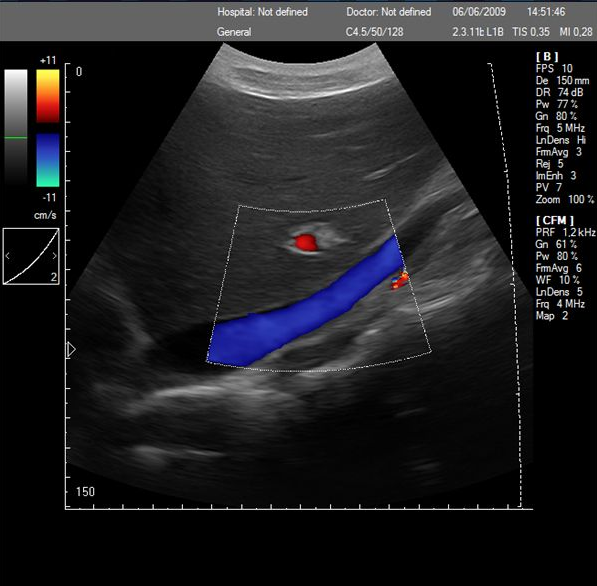

Touch screen color doppler,Protable color doppler,22" color doppler with convet probe SGC6

-Imaging Mode: B, BB, M, CD, PWD, CWD, DirPwr, Pwr

· Color Doppler (CFM)

Color Doppler

Touch screen color doppler,Protable color doppler,22" color doppler with convet probe SGC6 Images